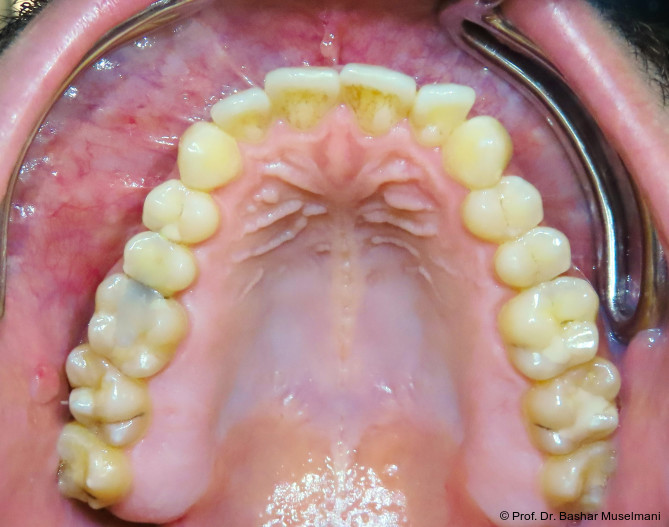

Abschlussbefund

Die Behandlung wurde mit 0.018 x 0.0275" TMA-Bögen abgeschlossen. Nach Entfernung der Multibracketapparatur zeigten sich:

• eine stabile Klasse I-Verzahnung

• ein normalisierter Overjet und Overbite

• deutliche Verbesserung der okklusalen Interdigitation

• ein ästhetisch harmonisiertes Profil

Die Behandlungsphase wird mit dem Einsetzen von TMA-Bögen im Ober- und Unterkiefer abgeschlossen (Abb. 10a–e). In den Abbildungen 11a bis c sind die extraoralen Aufnahmen nach Behandlungsabschluss und nach Entfernung der Brackets in beiden Kiefern dargestellt. Die Aufnahmen und die Kephalometrischen Analysen zeigen deutliche und rasche Veränderungen zwischen Behandlungsbeginn und -ende. Die Kephalometrischen Werten sind dabei von besonderer Bedeutung. Wie sich deutlich anhand des vergleiches der drei Behandlungsphase erkennen lässt.

Ende

• SNA: 82,0°

• SNB: 81,5°

• ANB: 0,6°

• Wits-Wert: +0,7 mm

Der Patient stellte sich erneut an der Universitätsklinik zur Beurteilung seines Zustands vor. Es wurde berichtet, dass keine chirurgische Behandlung der Dysgnathie mehr erforderlich ist.